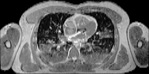

Visible Human male: Sectio transversalis 1437

CT

NMR

Pd                          / T2 \                         T1